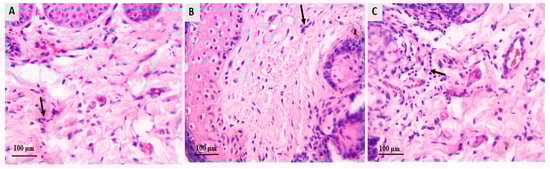

Skin biopsies were subjected to histopathological analysis using H&E and PAS staining to assess changes in epidermal structure and levels of inflammation. Skin samples were collected at two key time points: before and after the treatment protocol’s completion. The results are presented in Figure 6 and Figure 7. In groups A and B, guinea pigs received different treatments: LCZ simple gel in group A and LCZ-NLC gel in group B. H&E staining showed significant thinning of the epidermis in both treatment groups compared to untreated controls (Figure 6A,B). Moreover, these groups demonstrated reduced inflammation severity in the dermal layers (Figure 7A,B). Skin samples from infected guinea pigs treated with NLC exhibited a spongiotic psoriasiform epidermis with a parakeratotic stratum corneum (Figure 6C). There was also prominent neutrophilic infiltration in the epidermis and a mixed inflammatory cell presence in the upper dermis (Figure 7C). Conversely, skin specimens from untreated guinea pigs in group D revealed even more excellent epidermal thickening and hyperkeratosis (Figure 6D). Additionally, PAS-stained sections from the same group (group D) showed fungal hyphae within the hyperkeratotic stratum corneum (Figure 6E). These histological changes across all groups were consistent with findings from direct KOH microscopy and fungal culture studies, underscoring the effects of the various treatments on skin pathology.

Figure 7.

Histologic features of the guinea pig model of dermatophytosis following treatment with LCZ simple gel, LCZ-NLC gel, NLC gel (placebo), terbinafine cream, and untreated controls. Images depict (A) infected group A after LCZ simple gel, (B) group B after LCZ-NLC gel, and (C) group C after NLC gel treatment, taken four weeks after treatment. Groups treated with luliconazole (LCZ simple gel and LCZ-NLC gel) showed a notable reduction in inflammation and inflammatory cell infiltration in the dermal layers, indicated by black arrows. In contrast, the NLC-gel-treated group exhibited significant inflammatory cell infiltration, also highlighted by black arrows. All images were captured at a magnification of 40×.